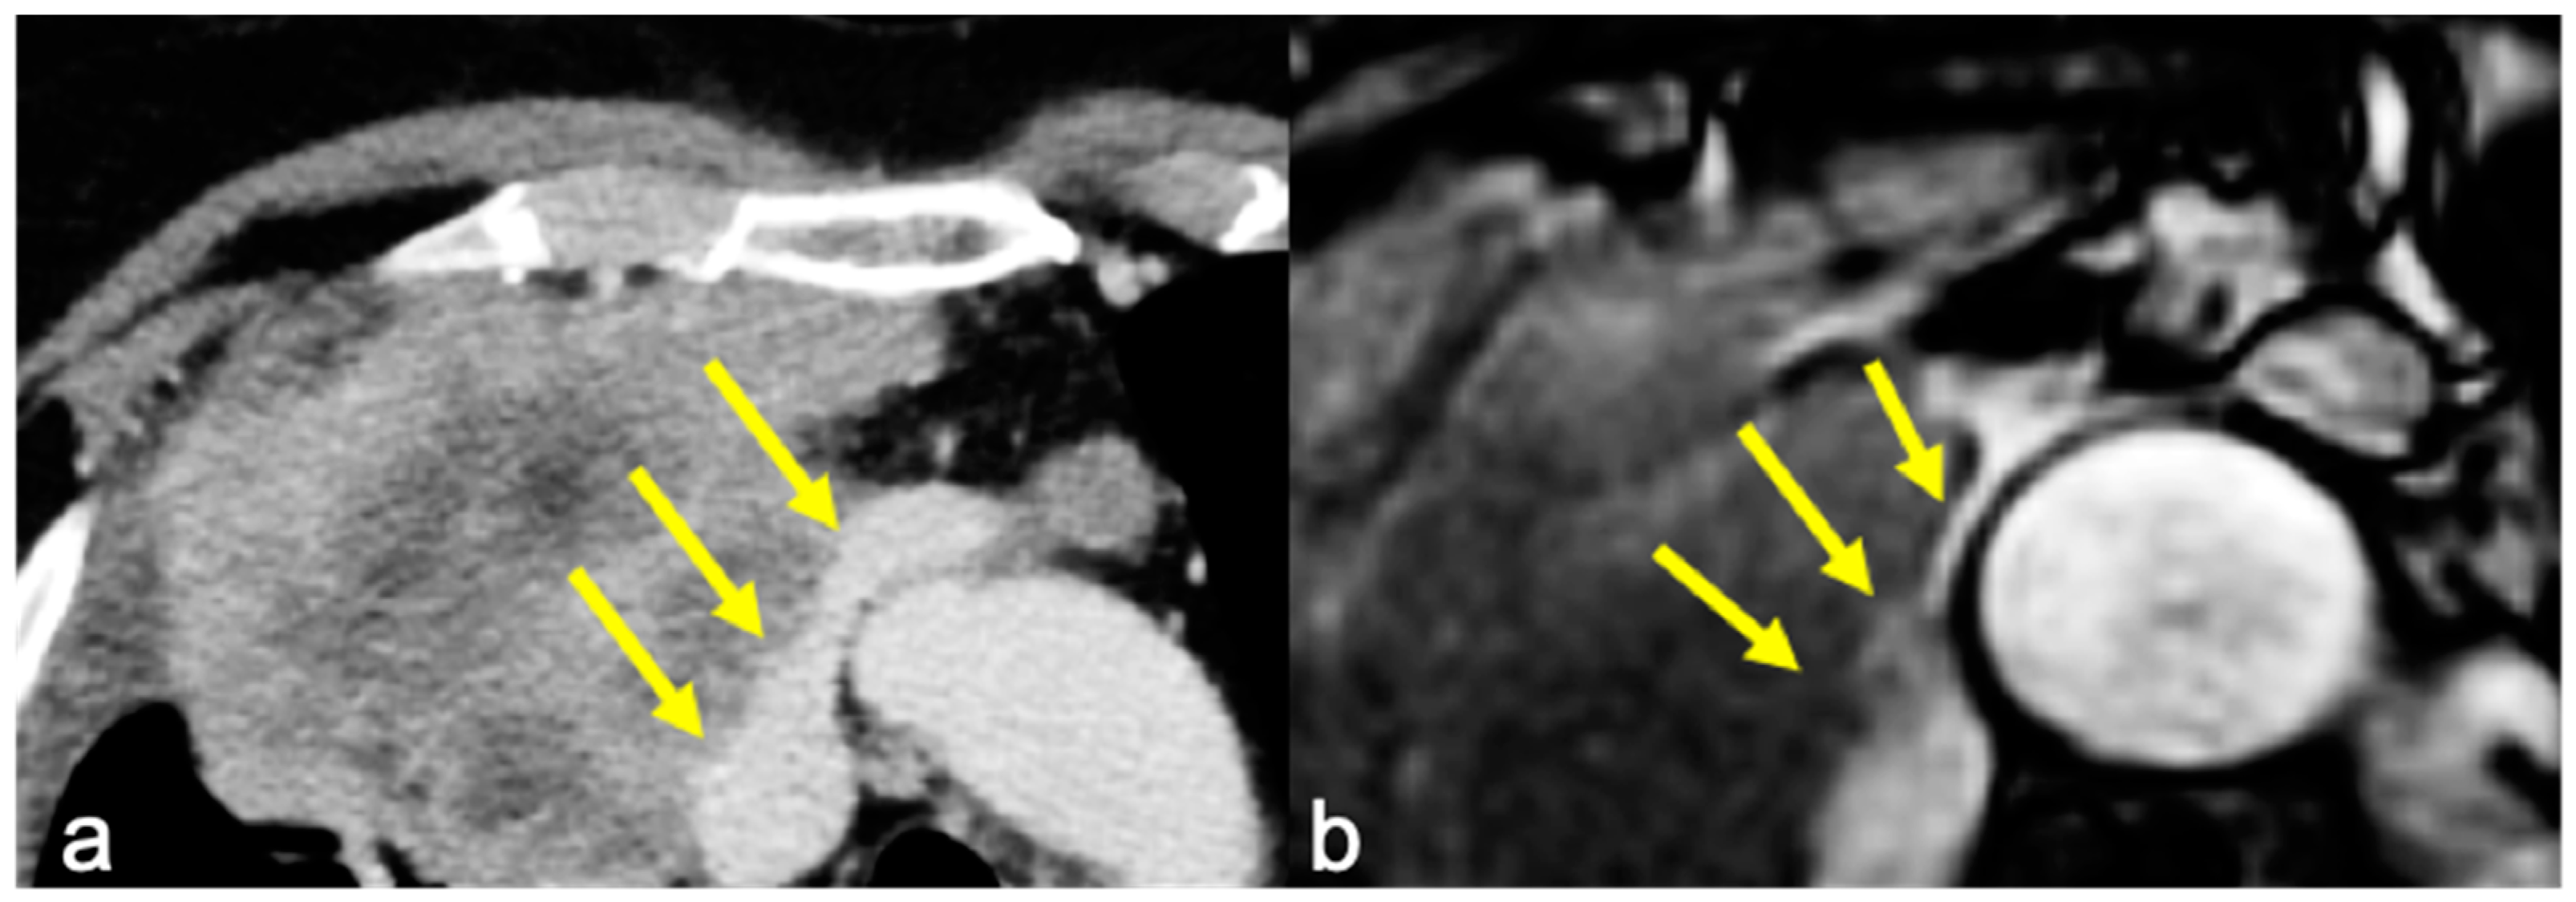

Infiltration was evaluated on the basis of the radiological reports of both CT and cine-MRI. On the contrast-enhanced CT scans, infiltration was reported when adipose tissue cleavage between the mass and the surrounding cardiovascular structures was absent. On cine-MRI, direct invasion was confirmed by the absence of the sliding motion between the mass and the heart and—for extracardiac sites—by the absence of the “India-Ink” artifact between the mass and the adjacent structures (Figure 1 and Figure 2). The surgical approach was defined after a multidisciplinary meeting where CT and MRI images of a single case were studied by radiologists and surgeons.

Figure 4. The case of a 50 y.o. patient affected by a mediastinal sarcoma in which pre-operative chest CT posed the suspicion of ascending aorta infiltration by the mass: image (a) shows the absence of adipose tissue cleavage between the mass and the aorta (yellow arrows) in the axial plane. Cine-MRI (image (b)) shows the “India Ink” artifact between the vessel and the mass (yellow arrows), excluding the presence of infiltration. Intraoperative evidence and final histological report confirmed cine-MRI findings, excluding vascular infiltration.